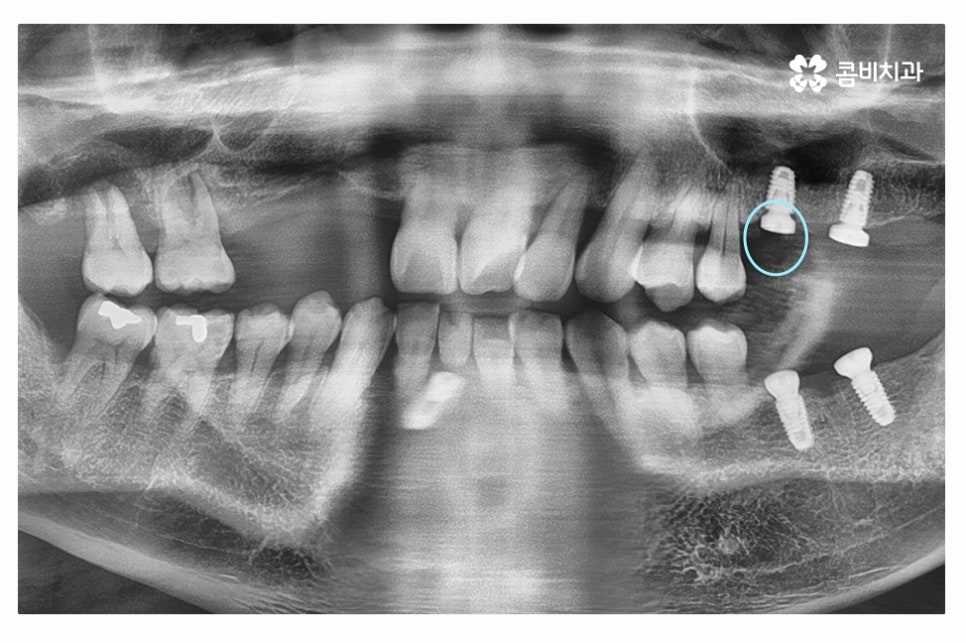

위 이미지처럼 인공치근이 잇몸뼈와 단단하게

골 유착 과정을 거치면 자연치아와 거의 비슷한 수준의 저작력을 회복할 수 있어요.

수술이 잘 된 경우 환자분의 치아의 모양에 맞게 어버트먼트를 제작하기 위하여

위 사진처럼 코핑이라는 것을 연결하고 임상을 뜨는 과정을 거친다고 볼 수 있어요